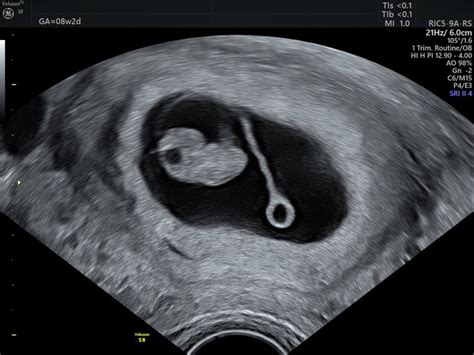

Nezdravljena nosečnostna sladkorna bolezen lahko vodi do nepravilnega razvoja centralnega živčnega sistema, srca in velikih žil pri plodu. Otrok je lahko večji od povprečja (makrosomija), kar poveča možnost za obporodne poškodbe tako otroka kot mame. V skrajnih primerih lahko nezdravljena nosečnostna sladkorna bolezen povzroči celo plodovo smrt pred ali tik po rojstvu. Ravno zato je natančno spremljanje ploda med nosečnostjo ključnega pomena, kar vključuje pogostejše ultrazvoke za nadzor rasti in razvoja. Otroci, rojeni materam z gestacijskim diabetesom, imajo večjo verjetnost za razvoj debelosti in sladkorne bolezni tipa 2 kasneje v življenju.